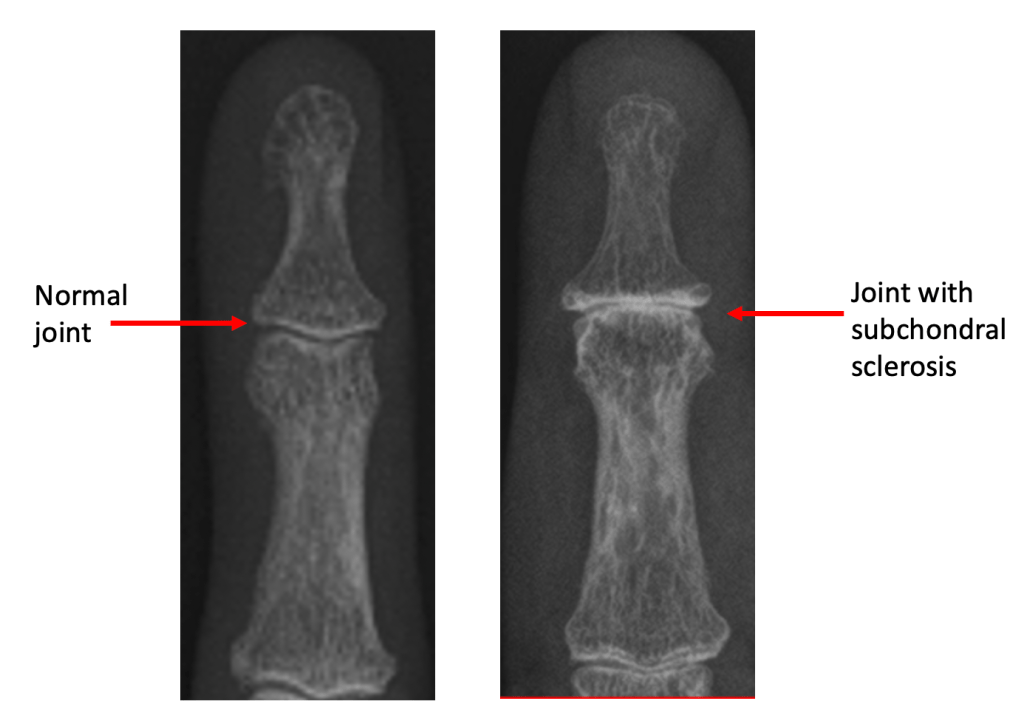

Subchondral Sclerosis

Subchondral simply means ‘under the cartilage‘, and sclerosis is the name given when bone appears thicker or whiter on an xray. When cartilage is lost from the joint, bone articulating with bone triggers a process where the body tries to increase the density of the remaining bone to protect it – on an xray, this gives an appearance of whiteness around the joint, because less xrays can pass through this thickened bone and make it to the xray plate.